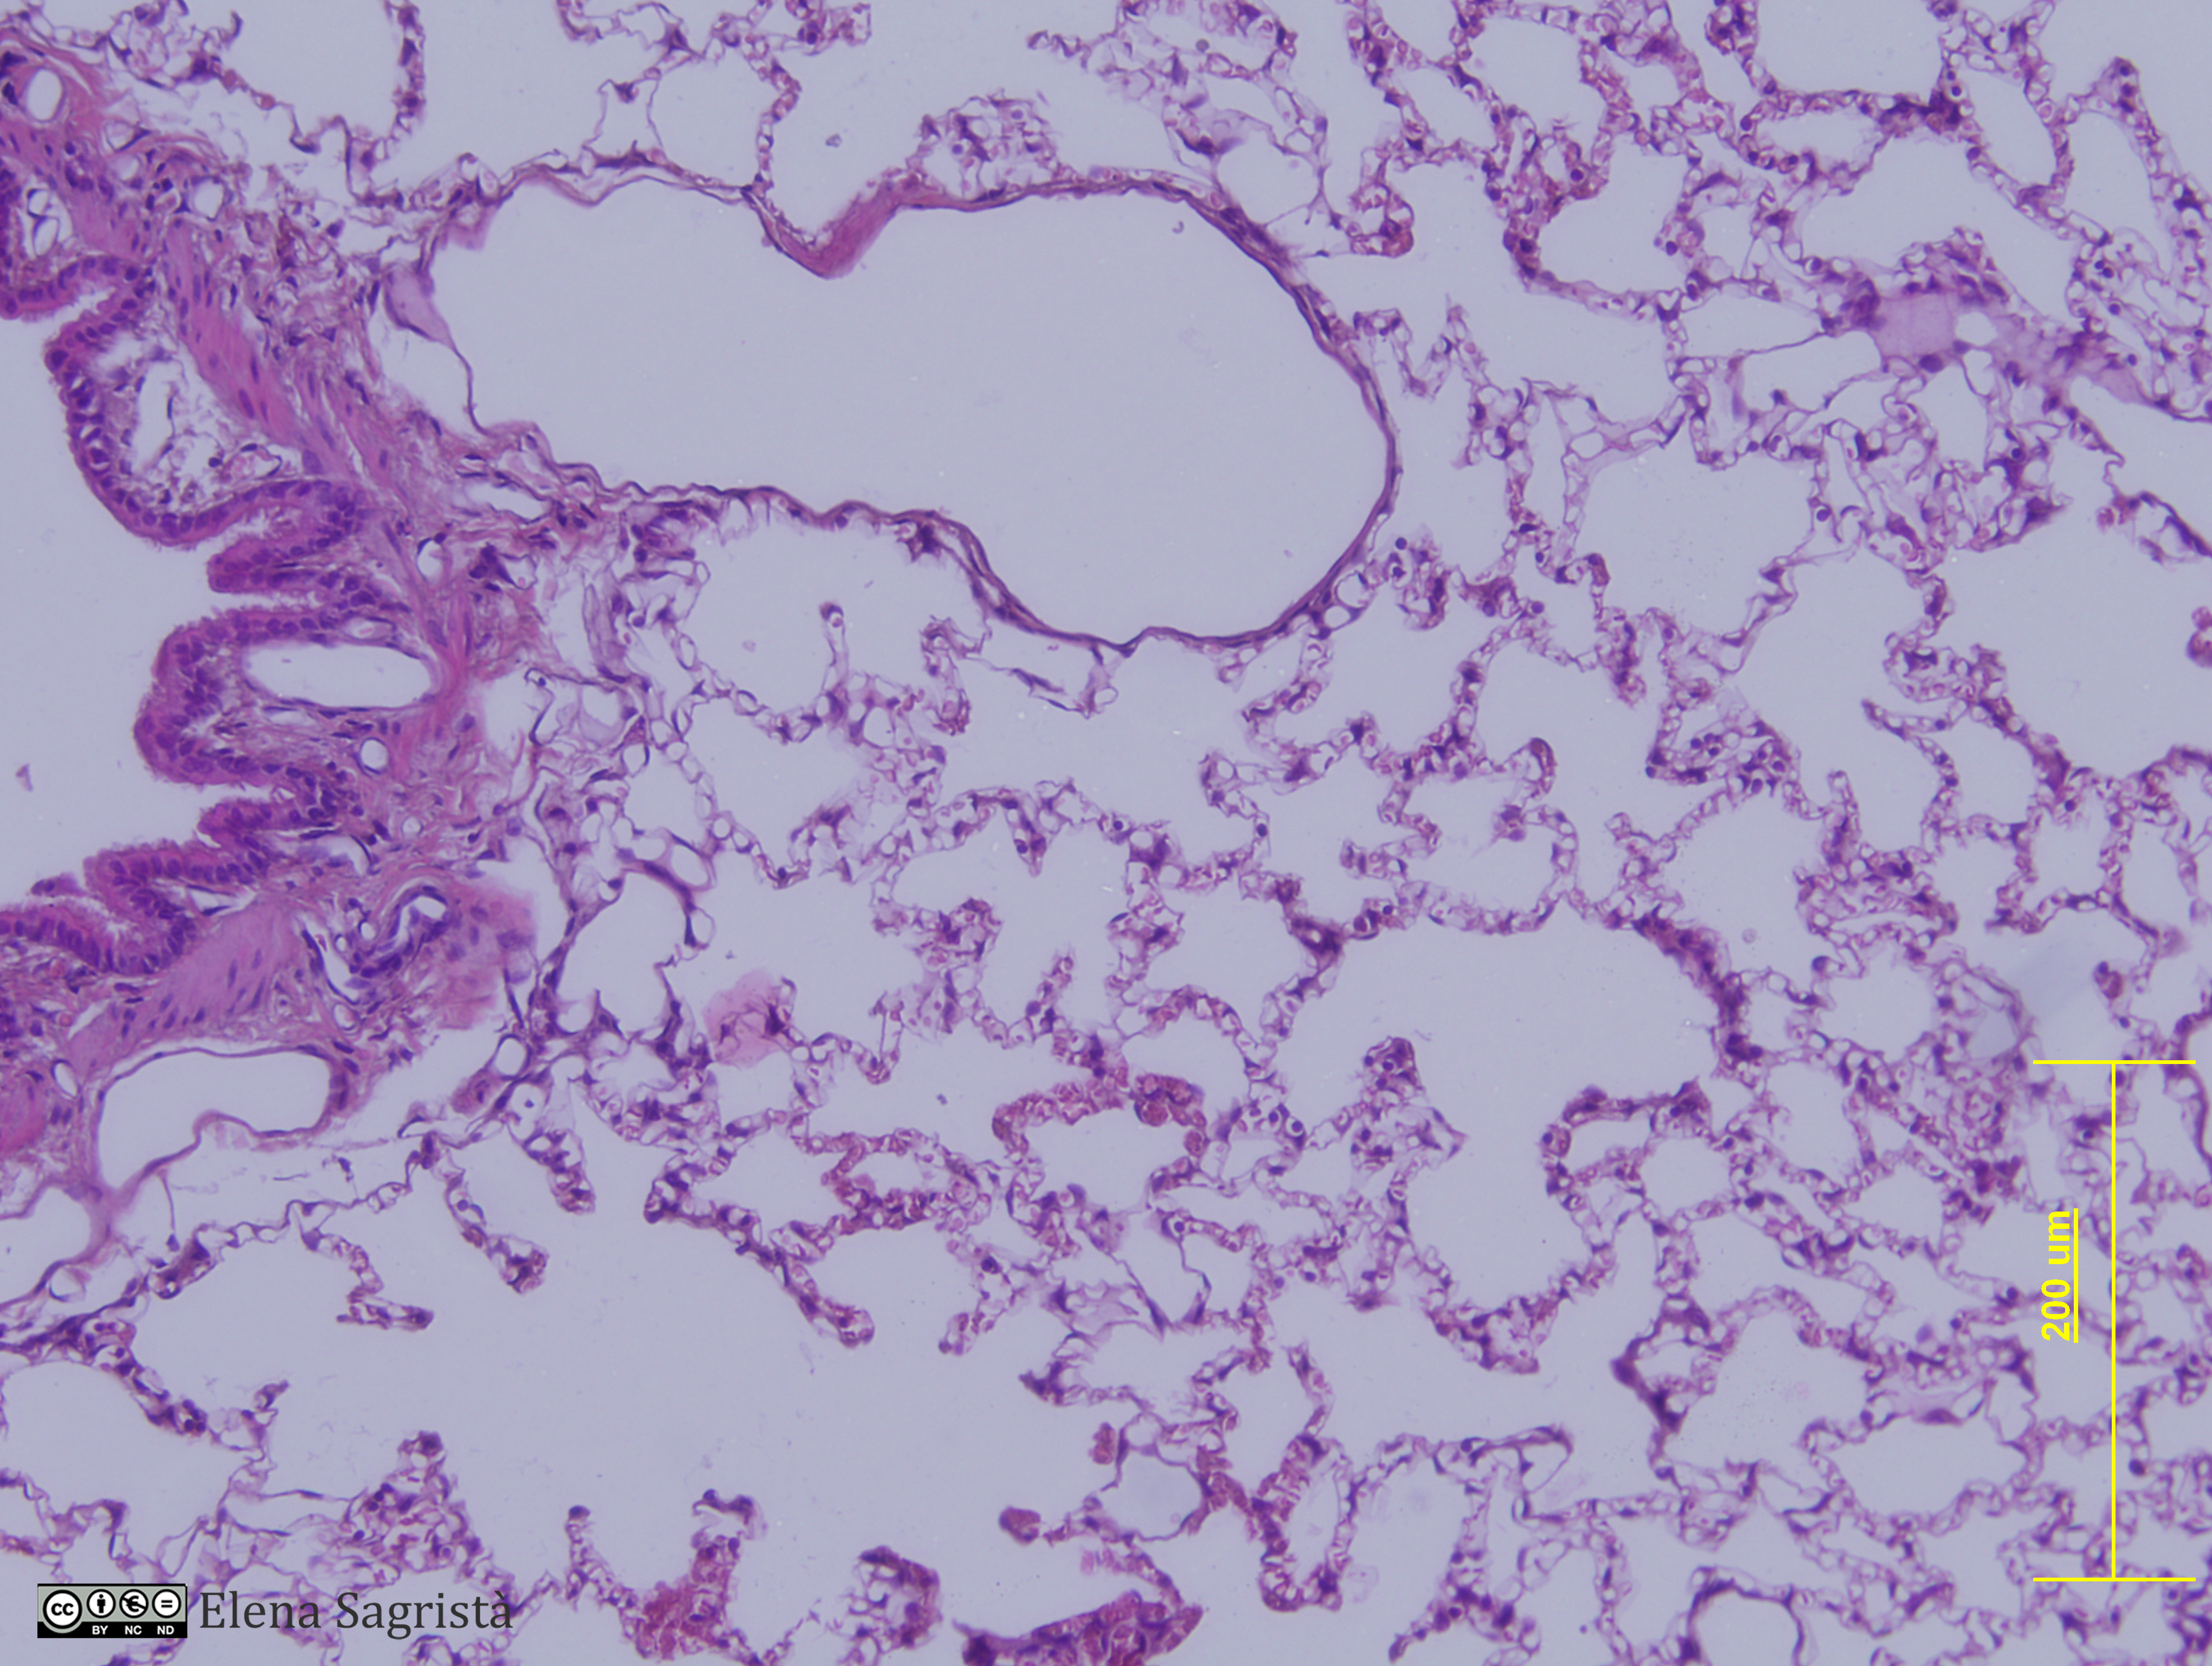

Histologia imatges: 13 Pulmó

Imatges de preparacions histològiques de Pulmò. Microscopia òptica.